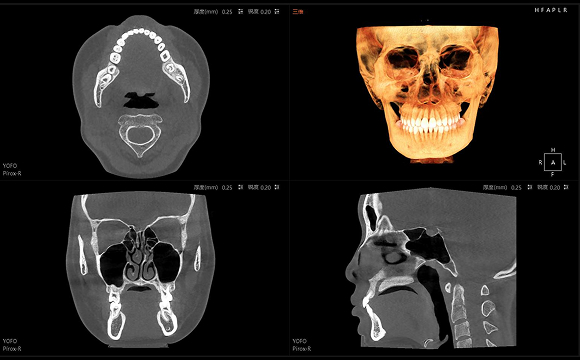

只需一次单圈扫描即可获得CT、3D全景和3D正/侧位影像,并能同时生成3D TMJ视图

提高诊疗效率,避免过度检查,减少患者所受的辐射

• CT

CT

• 3D全景

3D全景

• 3D 正侧位

3D 正侧位

• 3D TMJ视图

3D TMJ视图